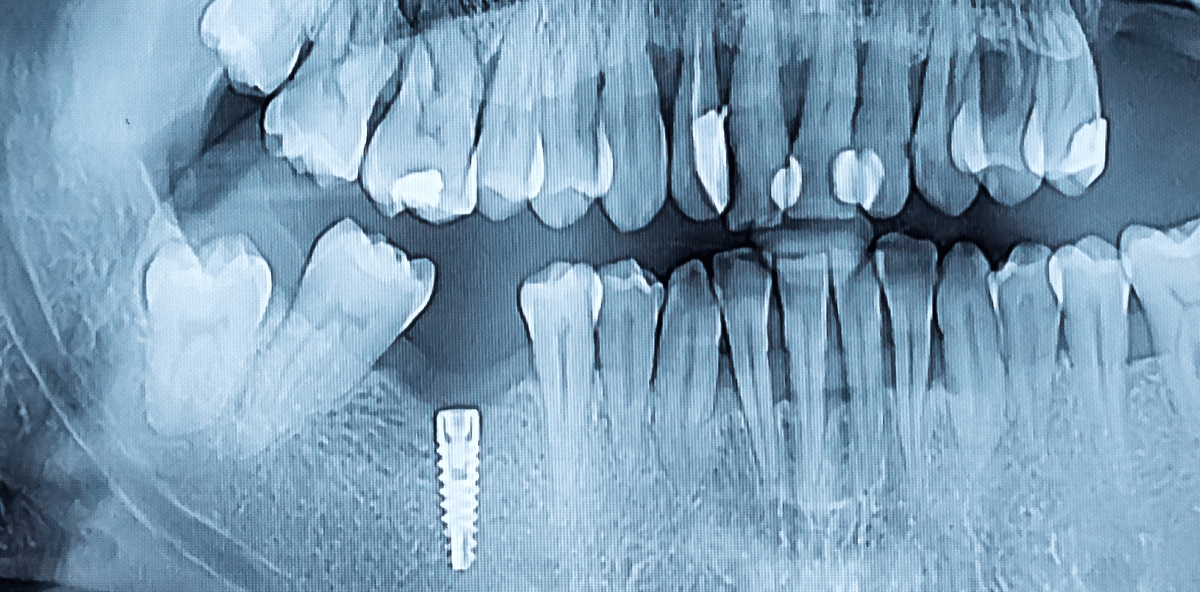

Risiko Rauchen und Osseointegration: So bleiben Implantate erhalten

Rauchen ist nicht nur schlecht für die Allgemeingesundheit, sondern auch für die Mundgesundheit, wie Studien zu Parodontitis, Karies und Co. belegen. Auch beim Thema Zahnersatz scheinen Raucher schlechtere Karten zu haben, wie Untersuchungen zu Zahnimplantaten zeigen. Eine brasilianische Analyse hat sogar spezielle Implantate mit sandgestrahlter und säuregeätzter Oberfläche untersucht.

Ob Zahnimplantate eine lange Lebenszeit im Patientenmund haben, ist von verschiedenen Faktoren abhängig. So steht beispielsweise Rauchen im Verdacht, die erfolgreiche Osseointegration, einer der Hauptgründe, warum Zahnimplantate dauerhaft im Kiefer halten, negativ zu beeinflussen. Mit dem Einsatz von Implantaten, die eine sandgestrahlte und säuregeätzte Oberfläche haben, sollte die Einheilung begünstigt werden.

Die brasilianische Studie hat dazu 22 Patienten untersucht – 11 Raucher und 11 Nichtraucher. Jeder Teilnehmer erhielt ein Mikroimplantat, das nach acht Wochen wieder entfernt wurde. Für die Analyse entnahmen die Forscher außerdem Biopsien der umliegenden Gewebe. Die Ergebnisse zeigten, dass die Osseointegration bei den Nichtrauchern weiter fortgeschritten war, als bei den Rauchern. So haben Raucher auch weiterhin – trotz der Verwendung spezieller Zahnimplantate – schlechtere Karten beim dauerhaften Zahnersatz. Hilft nur, mit dem Rauchen aufzuhören!

Quelle: Clinical Oral Implants Research